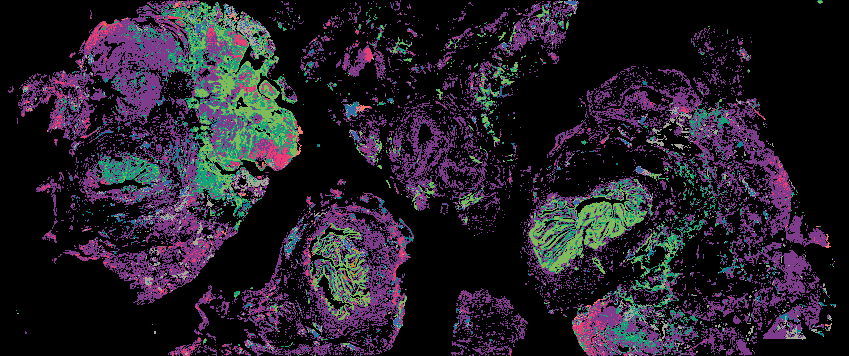

Ovarian STIC Spatial Transcriptomic Data from GeoMX and Multiplex Imaging

Ovarian Cancer with Annotation - LSP15327

Ovarian Cancer with Annotation - LSP15343